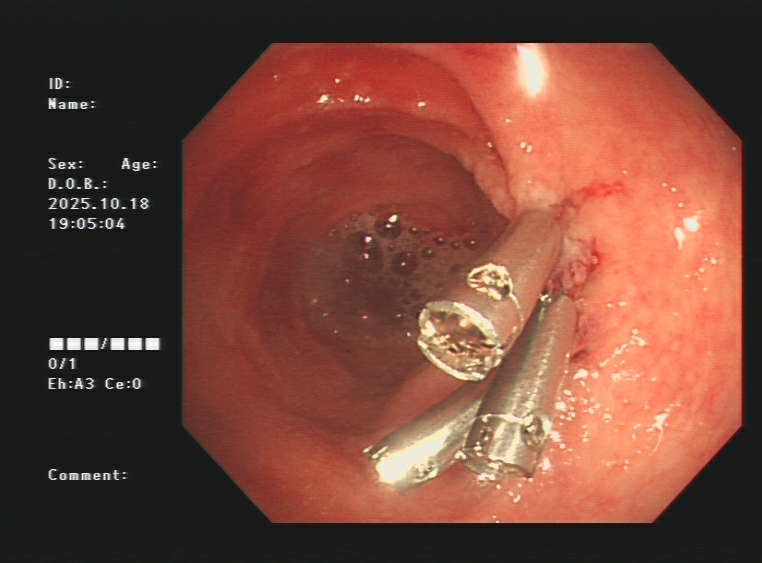

1.上消化道出血常见原因:消化性溃疡(胃溃疡、十二指肠溃疡)、食管炎、急性糜烂出血性胃炎、上消化道肿瘤(食管癌、胃癌)、剧烈呕吐造成的食管贲门黏膜撕裂伤、肝硬化引起的食管胃底静脉曲张。以下是一些常见的上消化道出血内镜图片:

急性胃黏膜病变出血、十二指肠球部溃疡出血及镜下止血夹止血